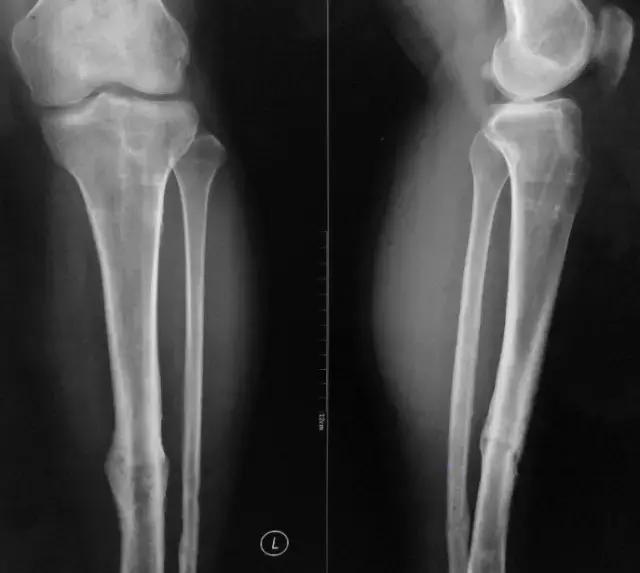

患者男,27岁, 5年前因左腔骨中下段开放骨折入院行交锁髓内钉固定术,切口一期愈合拆线出院。约2年前行内固定取出术,术后恢复良好。2个月前右膝髌韧带切口处时常出现破溃流脓(曾切开未发现线结)。市人民医院分泌物涂片检查示少许白细胞。现诊断疑为骨髓炎?现左小腿无疼痛,无发热,无特殊感觉。

影像检查

诊断:感染。 检查:膝关节MRI,确认伤口窦道是否与髓腔相通。 治疗:1、血沉和C反应蛋白正常,目前无需特殊处理。 2、如果窦道反复出现或血沉和C反应蛋白升高可考虑手术。如证明窦道与髓腔相通,需行扩髓。